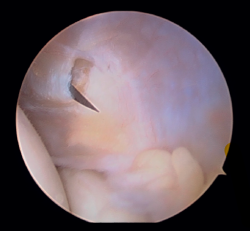

En primer lugar, se realiza el portal anteromedial de visión, incidiendo únicamente la piel y realizando disección roma con un mosquito recto. A continuación, se introduce la vaina del artroscopio, atravesando de forma anterior y proximal el septo fibromuscular medial, en dirección a la cabeza del radio, de forma posterior y distal, para evitar lesionar el nervio cubital y el paquete vascular anterior del codo. Una vez introducida la óptica en el portal medial, se procede a realizar el portal lateral proximal como portal de trabajo. Se realiza bajo visión directa, utilizando como guía una aguja intramuscular de fuera a dentro, para localizar el punto de entrada que permita mejor ángulo de trabajo (Figura 4). Posteriormente, se incide en la piel y se realiza disección roma con un mosquito recto para entrar en la articulación (Figura 5).

Figura 5. Realización del portal lateral (paciente en decúbito lateral, codo derecho, visión desde el portal medial).